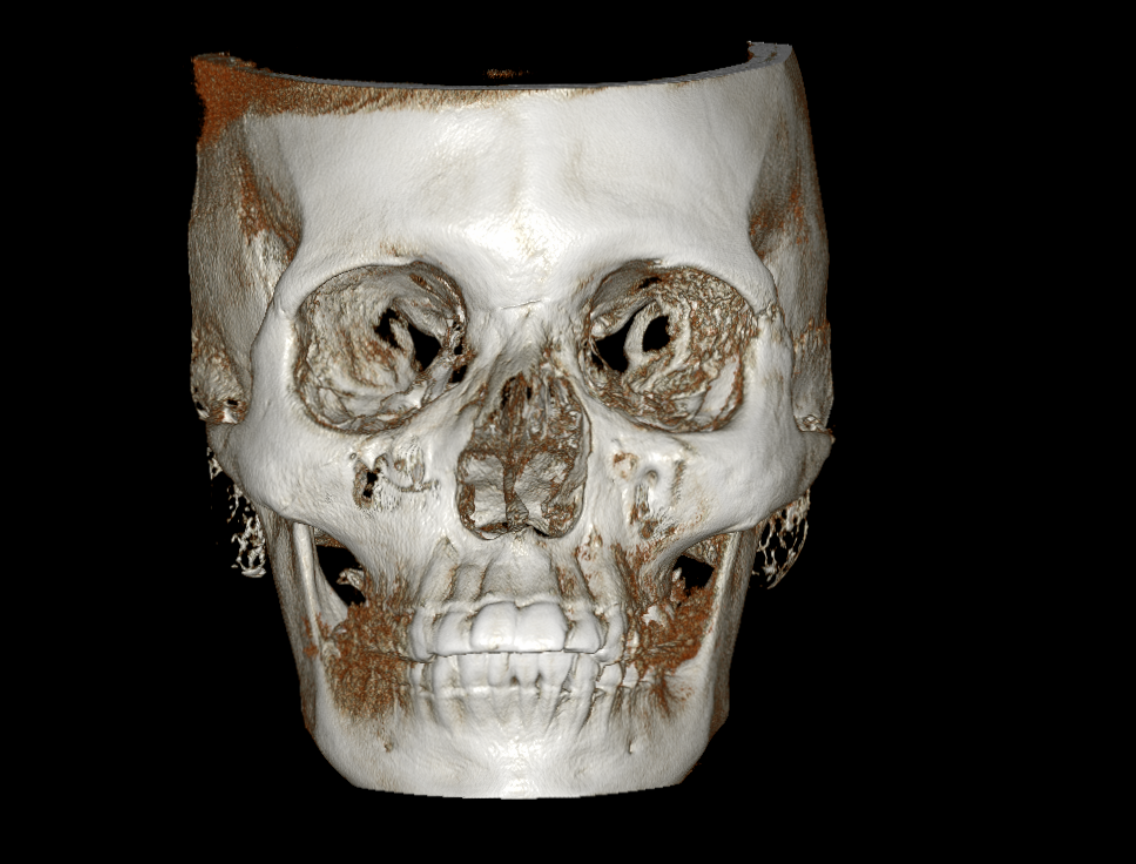

Cone Beam de alta resolución con FOVs múltiples. Reconstrucciones volumétricas para implantología, ortodoncia, endodoncia y cirugía maxilofacial.